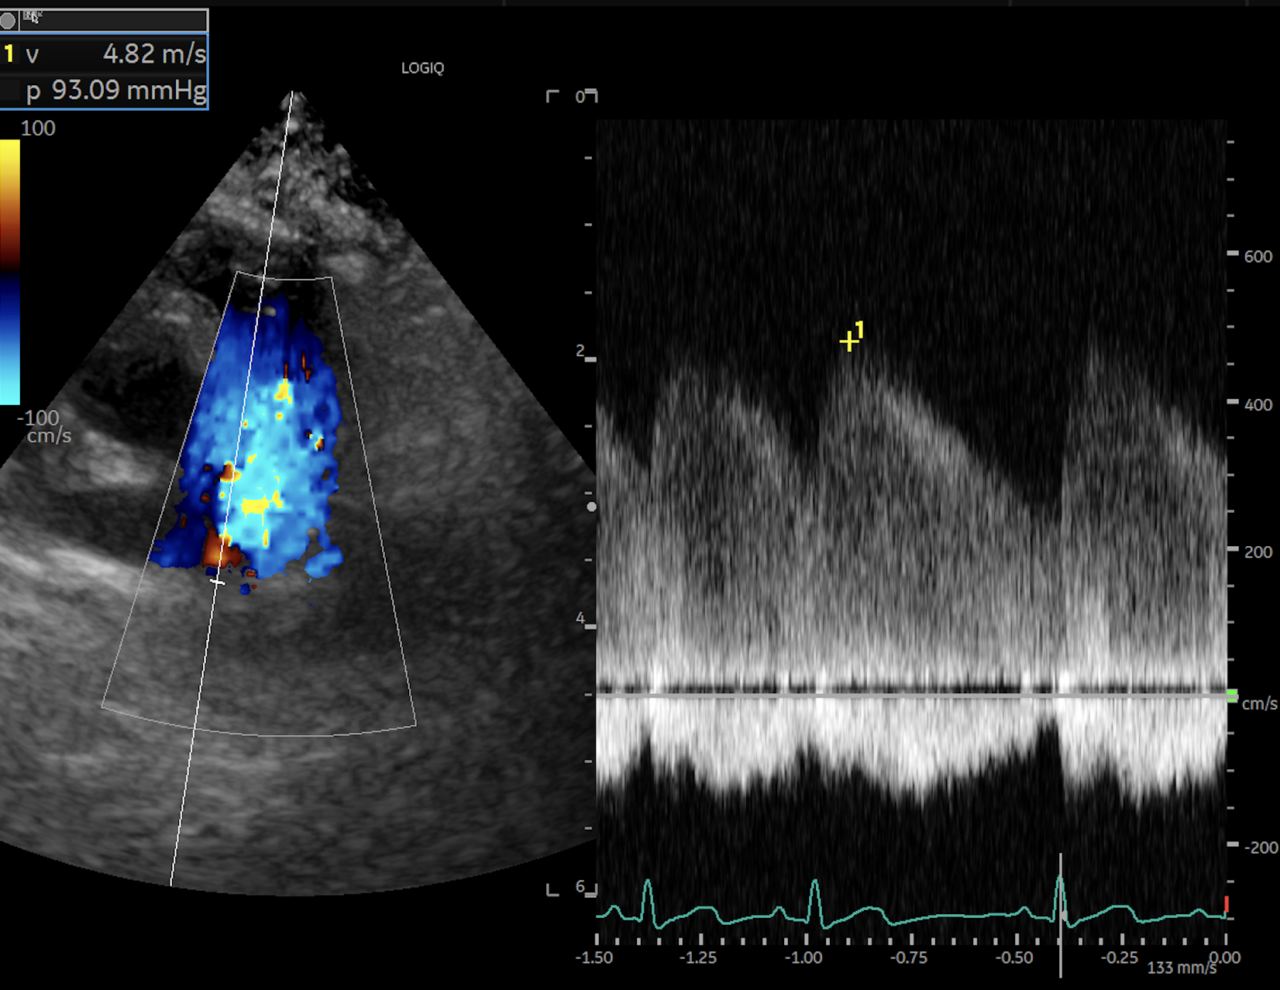

PDAの確定診断は心エコー検査が必要ですが、超音波を当てれば比較的簡単に診断できます。超音波検査で下行大動脈から左肺動脈へと向かう短絡血流を確認することが必要です。

様々なパターンの逆流(モザイクになってる部分が血液の逆流が起こっている)

逆流している血液の波形

病気が確定出来たら検査時点での病状の状態を把握する必要があるため、レントゲンや心電図、血液検査などを含めた心機能検査をして手術の予定を決めます。心機能検査のための超音波はとても重要でこれは血液の流速や、動脈管の太さなどなるべく正確に知りたいので多少の技術が必要です。その血流波形を確認して最大血流速度が3.5m/sec以下の場合は、肺高血圧症の合併症も疑わなければならないため、検査による描出と計測はとても重要です。